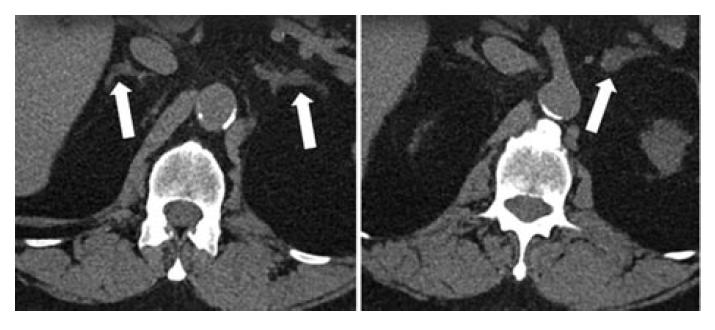

При проведении КТ выявлены узелок в левом надпочечнике, а также небольшое утолщение в правом надпочечнике (рис. 2).

Рис. 2. КТ-снимки 67-летнего пациента с ПГА в аксиальной проекции. Узелок в левом надпочечнике и участок утолщения в правом надпочечнике [3].